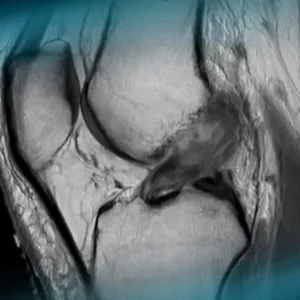

A 48-year-old female professional rower sustained a right knee injury in a motor accident, presenting with pain, swelling, and a range of motion (ROM) limited to 0–90 degrees. Physical examination revealed a positive Lachman test.